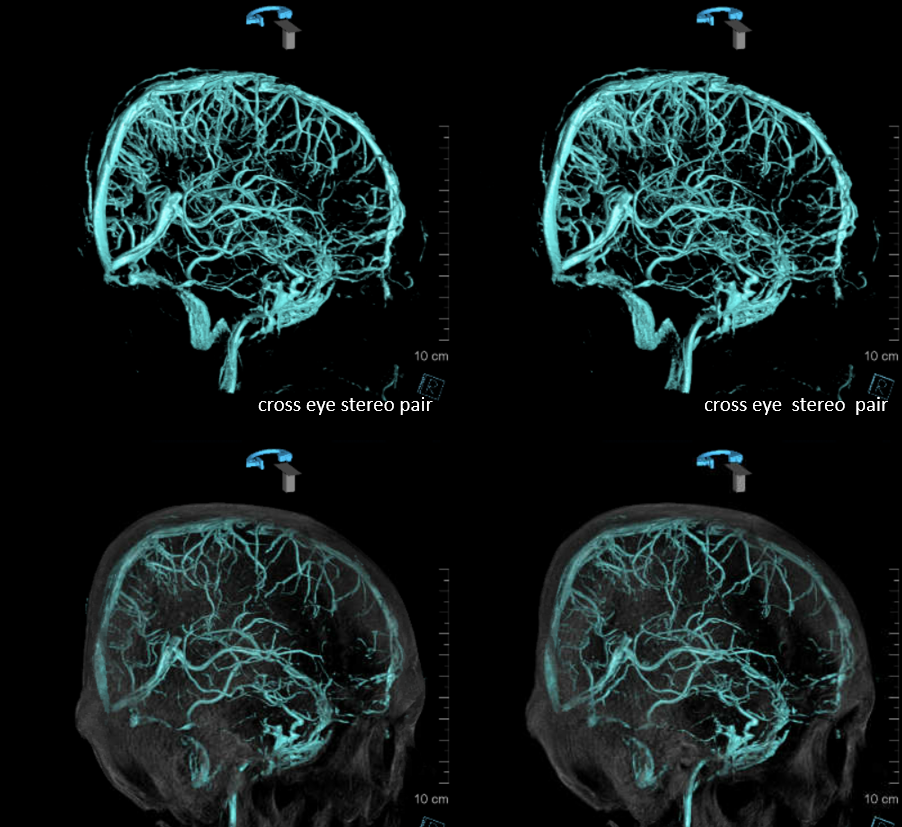

Following embolization, resection, recurrence (as frequently the case with childhood AVMs) and gamma-knife, things look good. Stereo, of course.

Following embolization, resection, recurrence (as frequently the case with childhood AVMs) and gamma-knife, things look good. Stereo, of course.